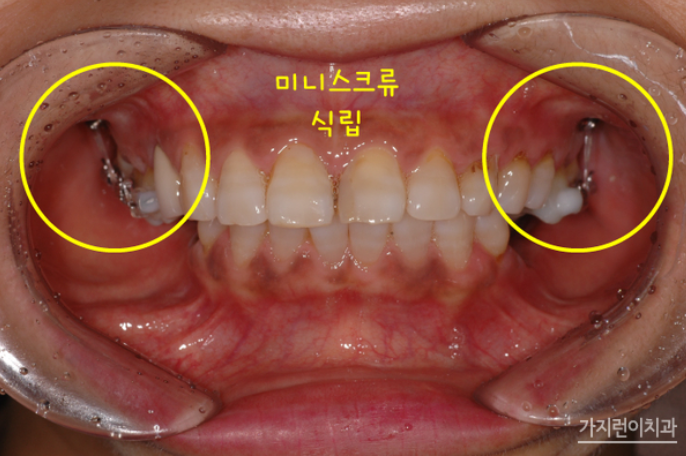

치아 상실 시 치료를 미루다가 방치하는 경우가 생각보다 많은데요. 치아 상실을 방치하면 빈 공간으로 치아가 이동하면서 치열이 무너질 수 있고, 또 잇몸 퇴축 현상이 일어나면서 추후 임플란트 시 문제가 될 수 있습니다. 그래서 환자분의 경우 치료를 통해 하악 구치부에 임플란트를 식립할 수 있었는데요. 상악 구치부의 함입을 위해 미니스크류를 식립했고 충분한 힘이 전해질 수 있도록 설계했습니다. 원래대로라면 하악 좌우 대구치 2개 및 제2소구치까지 모두 여섯 개의 임플란트가 필요했지만 이렇게 설계하면 임플란트를 4개만 심을 수 있었는데요.

구치 함입 치료를 시작하고 5개월이 되었을 때 하악구치부에 임플란트 기둥을 식립했는데요. 함입 치료 7개월 차에 임시크라운을 올렸습니다. 이 과정 역시 어려운 난이도인데요. 상하악 전치의 뻐드러짐이 개선되면서 후방으로 이동하는 양을 정확히 계산해야 하기 때문입니다.